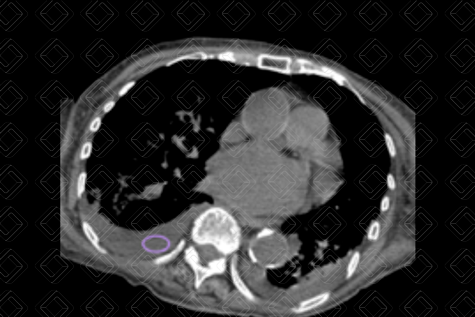

Descrição das figuras 1, 2 e 3: Adolescente de 16 anos, com desconforto respiratório e febre. Imagem A (figura 1): radiografia de tórax evidencia moderado derrame pleural (asterisco). Imagem B (figuras 2 e 3): exame foi complementado com tomografia de tórax com contraste, pela não melhora clínica. Observa-se o derrame pleural (seta vermelha) à direita e os nódulos centrolobulares (seta amarela) com padrão de árvore em brotamento à esquerda, achados muito sugestivos de tuberculose pulmonar, confirmada posteriormente.

• Radiografia de tórax : Em geral, os derrames livres acumulam-se nas porções pendentes dos pulmões. Na radiografia em ortostase, o achado mais precoce é a obliteração do seio costofrênico posterior na imagem em perfil. Volumes maiores passam a ser observados também na incidência frontal. Derrames pleurais volumosos podem ser uma das causas de hemitórax opaco, com aumento das dimensões do hemitórax acometido e desvio das estruturais mediastinais contralateralmente. Lembrando que o uso da radiografia em decúbito lateral com raios horizontais pode ser usado para confirmar o derrame pleural, mas está em desuso devido ao excesso de radiação ionizante (atualmente, nos casos duvidosos, a melhor escolha é a ultrassonografia de tórax). Figura 1;